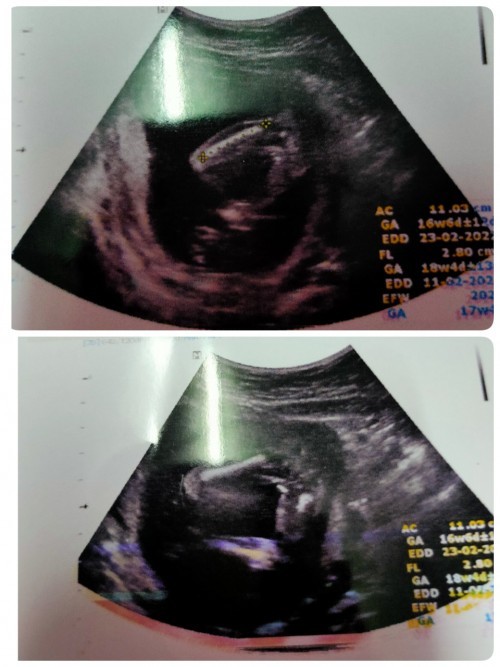

17wค่ะ คุณหมอบอกผู้ญ แต่ยังไม่คอนเฟิม100%